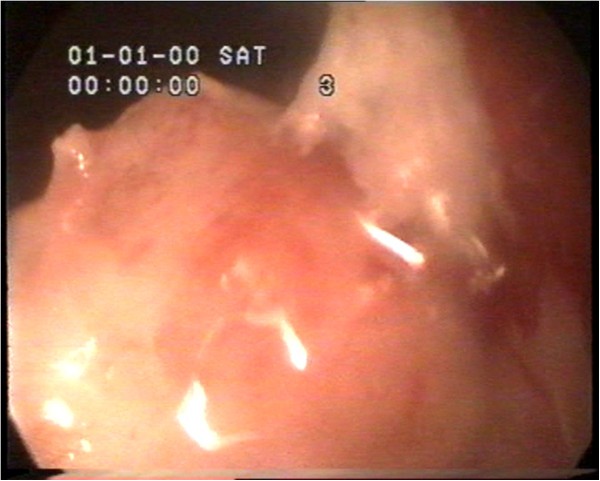

Analysis of the work found that glandular cystic hyperplasia of the endometrium occurs during anovulatory cycles which tend to be longer than the normal menstrual cycle after prolonged persistence of follicles, most of which frequently occur in women 40–45 years who are bleeding prior to amenorrhea for 1 and 2–5 months. The extended phase of anovulatory cycles results from prolonged high concentration of estrogen, resulting in endometrial hyperplasia which is processed as glandular (non-atypical complex hyperplasia) or glandular cystic (simple non-atypical hyperplasia) endometrial hyperplasia. A hysteroscopic image of glandular cystic hyperplasia is shown in Figure 1.

Figure 1

Hysteroscopic image of glandular cystic hyperplasia of the endometrium.